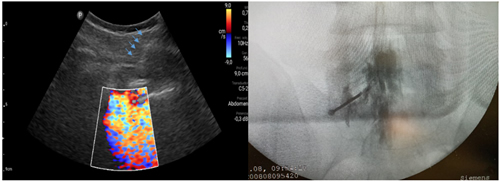

Pacientes y métodos: Un total de 25 pacientes con dolor radicular lumbosacro fueron seleccionados para recibir inyecciones epidurales interlaminares de esteroides en posición decúbito dorsal, utilizando la técnica ecoguiada en plano, en tiempo real, en eje corto o transversal. En todos los casos, un epidurograma de control fue realizado previo a la inyección de la solución de esteroides. El rendimiento de la técnica fue estudiado mediante la tasa de éxito de la misma, entendido como éxito a la obtención de un epidurograma sin necesidad de abandonar la técnica ecográfica en un tiempo menor a 10 minutos. El rendimiento del procedimiento fue estadísticamente evaluado por el método de la suma acumulativa (CUSUM), y la curva de aprendizaje aplicando este método fue construida.

Resultados: La distancia promedio desde la piel al complejo posterior evaluada por el escaneo ecográfico previo al procedimiento fue de 6,7 ± 1,8 cm. De los 25 procedimientos realizados, en 21 se alcanzó el espacio epidural sin ayuda de la fluoroscopia, en un tiempo promedio de 4,8 ± 1,2 minutos. Esto constituye una tasa de éxito del 84 %. En los cuatro procedimientos restantes el espacio epidural fue alcanzado con éxito mediante el uso complementario de la fluoroscopia.

5. Karmakar MK, Li X, Ho A, Kwok WH Chui PT. Real-time ultrasound-guided paramedian epidural access: evaluation of a novel in-plane technique. Br J Anaesth. 2009;102(6):845-54.

6. Elsharkawy H, Saasouh W, Babazade R, Soliman LM, Horn JL, Zaky Sh. Real-time Ultrasound-Guided Lumbar Epidural with Transverse Interlaminar View: Evaluation of an In-Plane Technique. Pain Med. 2019;20(9):1750-5.

7. Wang Y, Wang, G, Ma D, Li H. Real-Time Ultrasound-Guided Paramedian Epidural Access Using a Paramedian Transverse Oblique Scan: A Prospective Case Series. J Anesth Perioper Med 2018;5:70-6.

8. Li H, Kang Y, Jin L, Ma D, Liu Y, Wang Y. Feasibility of ultrasound-guided lumbar epidural access using paramedian transverse scanning with the needle in-plane: a comparison with paramedian sagittal scanning. J Anesth. 2020;34(1):29-35.

13. Riveros-Perez E, Albo C, Jimenez E, Cheriyan T, Rocuts A. Color your epidural: color flow Doppler to confirm labor epidural needle position. Minerva Anestesiol. 2019;85(4):376-83.

14. Yoon JS, Sim KH, Kim SJ, Kim WS, Koh SB, Kim BJ. The feasibility of color Doppler ultrasonography for caudal epidural steroid injection. Pain. 2005;118(1-2):210-4.